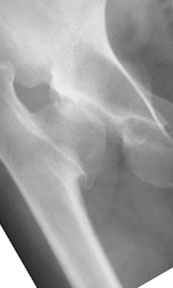

Pic. 1-5 preop plan; 6-8 similar case

Depending upon surgeon preference, as well as availability of adequate operating room equipment and staff, this reconstruction can be done in two stages: periacetabular osteotomy with correction of acetabular retroversion would be the first stage. The second stage would involve a proximal femoral valgus osteotomy with neck lengthening.

In this second stage, a 120 degree blade plate can be used for correction proximal femur varus deformity. These procedures are both technically difficult, and require a great amount of pre-operative planning, both by the surgeons involved as well as the operating room staff.